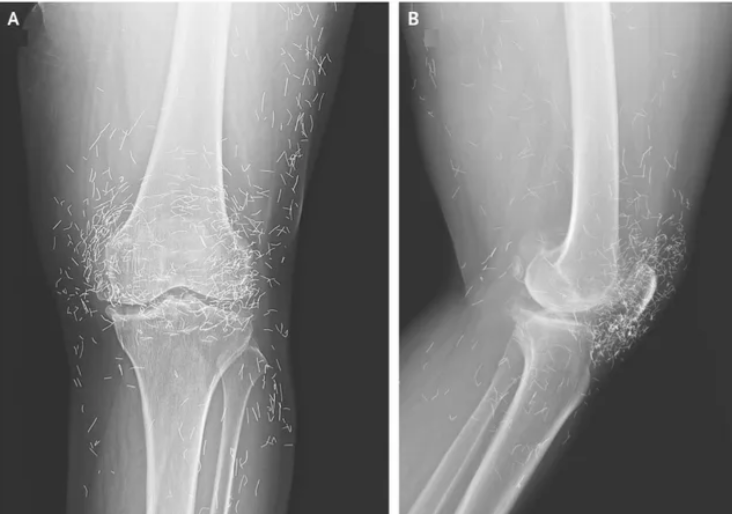

توجهت امرأة تعاني من ألم شديد في مفاصل ركبتيها إلى المستشفى في محاولة لمعرفة سبب آلامها المزمنة فأظهرت الأشعة السينية مئات الخيوط الذهبية الموجودة داخل ركبتها وفق ما ذكره تقرير لموقع "ساينس ديلي" .

وحين ازدادت وتيرة الألم ذهبت إلى المستشفى، فكشفت الأشعة السينية لركبتها اليسرى أن عظم الساق في الجزء الداخلي من المفصل قد ازداد سمكًا وصلابة. كما وُجدت نتوءات عظمية، على الأجزاء الداخلية من عظم الساق وعظم الفخذ بجوار مفصل الركبة.

ولكن الأهم هو ملاحظة الأطباء لمئات البقع في الأشعة السينية حول مفصل الركبة، والتي تبيّن أنها خيوط ذهبية صغيرة. وقال التقرير أن استنتاج الأطباء كان أن الخيوط قد أُدخلت كجزء من علاجات الوخز بالإبر للمرأة. وقد تُركت هذه الخيوط الذهبية القصيرة والمعقمة عمدًا في الأنسجة لتوفير تحفيز مستمر. وحذر التقرير من أن ترك الخيوط في مكانها ليس خاليًا من المخاطر، فقد أدى إلى تكوّن أكياس في حالات سابقة.